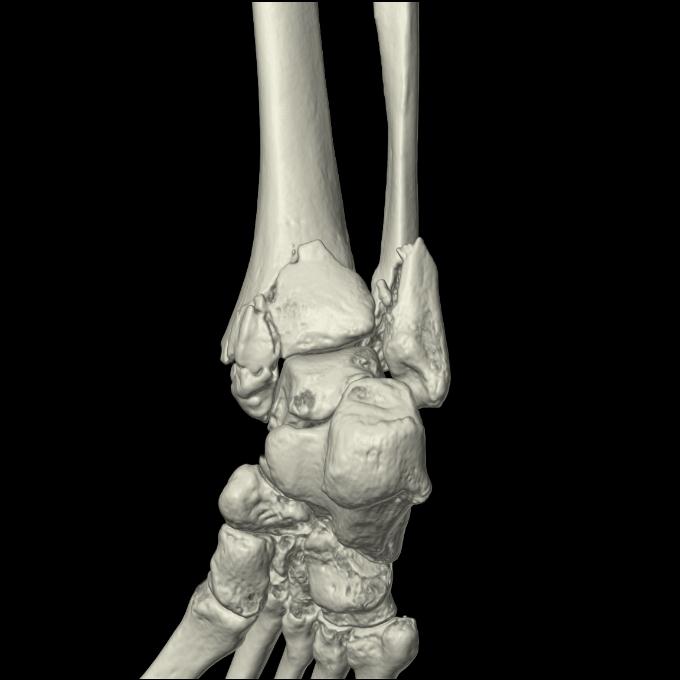

56476 8/28 4R 1/21 2R 左足関節 デジカメ写真 72歳女性 右足関節AS